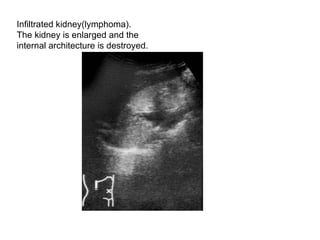

Renal lymphoma.A large hypoechoic tumor deposit is seen in

Infiltrated kidney(lymphoma).  The kidney is enlarged and the  internal architecture is destroyed.